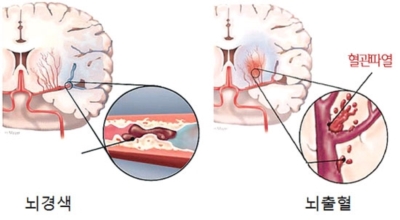

뇌경색의 경색이란 허혈성 괴사를 말해요. 여기서 허혈이란 혈관이 막히는 것을 말하고 괴사는 말 그대로 일부가 죽는 것을 말하는데 뇌경색의 경우 뇌의 혈관이 막혀 뇌세포 일부가 죽는 걸 의미해요. 뇌혈관이 막혔다 해서 혈액 공급이 안되는것은 또 아니에요.

막힌 혈관으로도 혈액이 공급되긴 하나 혈관이 막혀있어 혈액을 보내긴 하나 제대로 흐르지 못하고 혈액이 쌓이고 축적되어 물풍선에 물이 꽉 차서 터지듯 뇌혈관이 터지는 경우가 일어날 수 있는데 이를 뇌출혈 이라고 해요. 물론 외상으로 인한 뇌출혈도 있지만 이처럼 뇌경색으로 인해 혈관이 막혀 터지는 경우도 있어요.